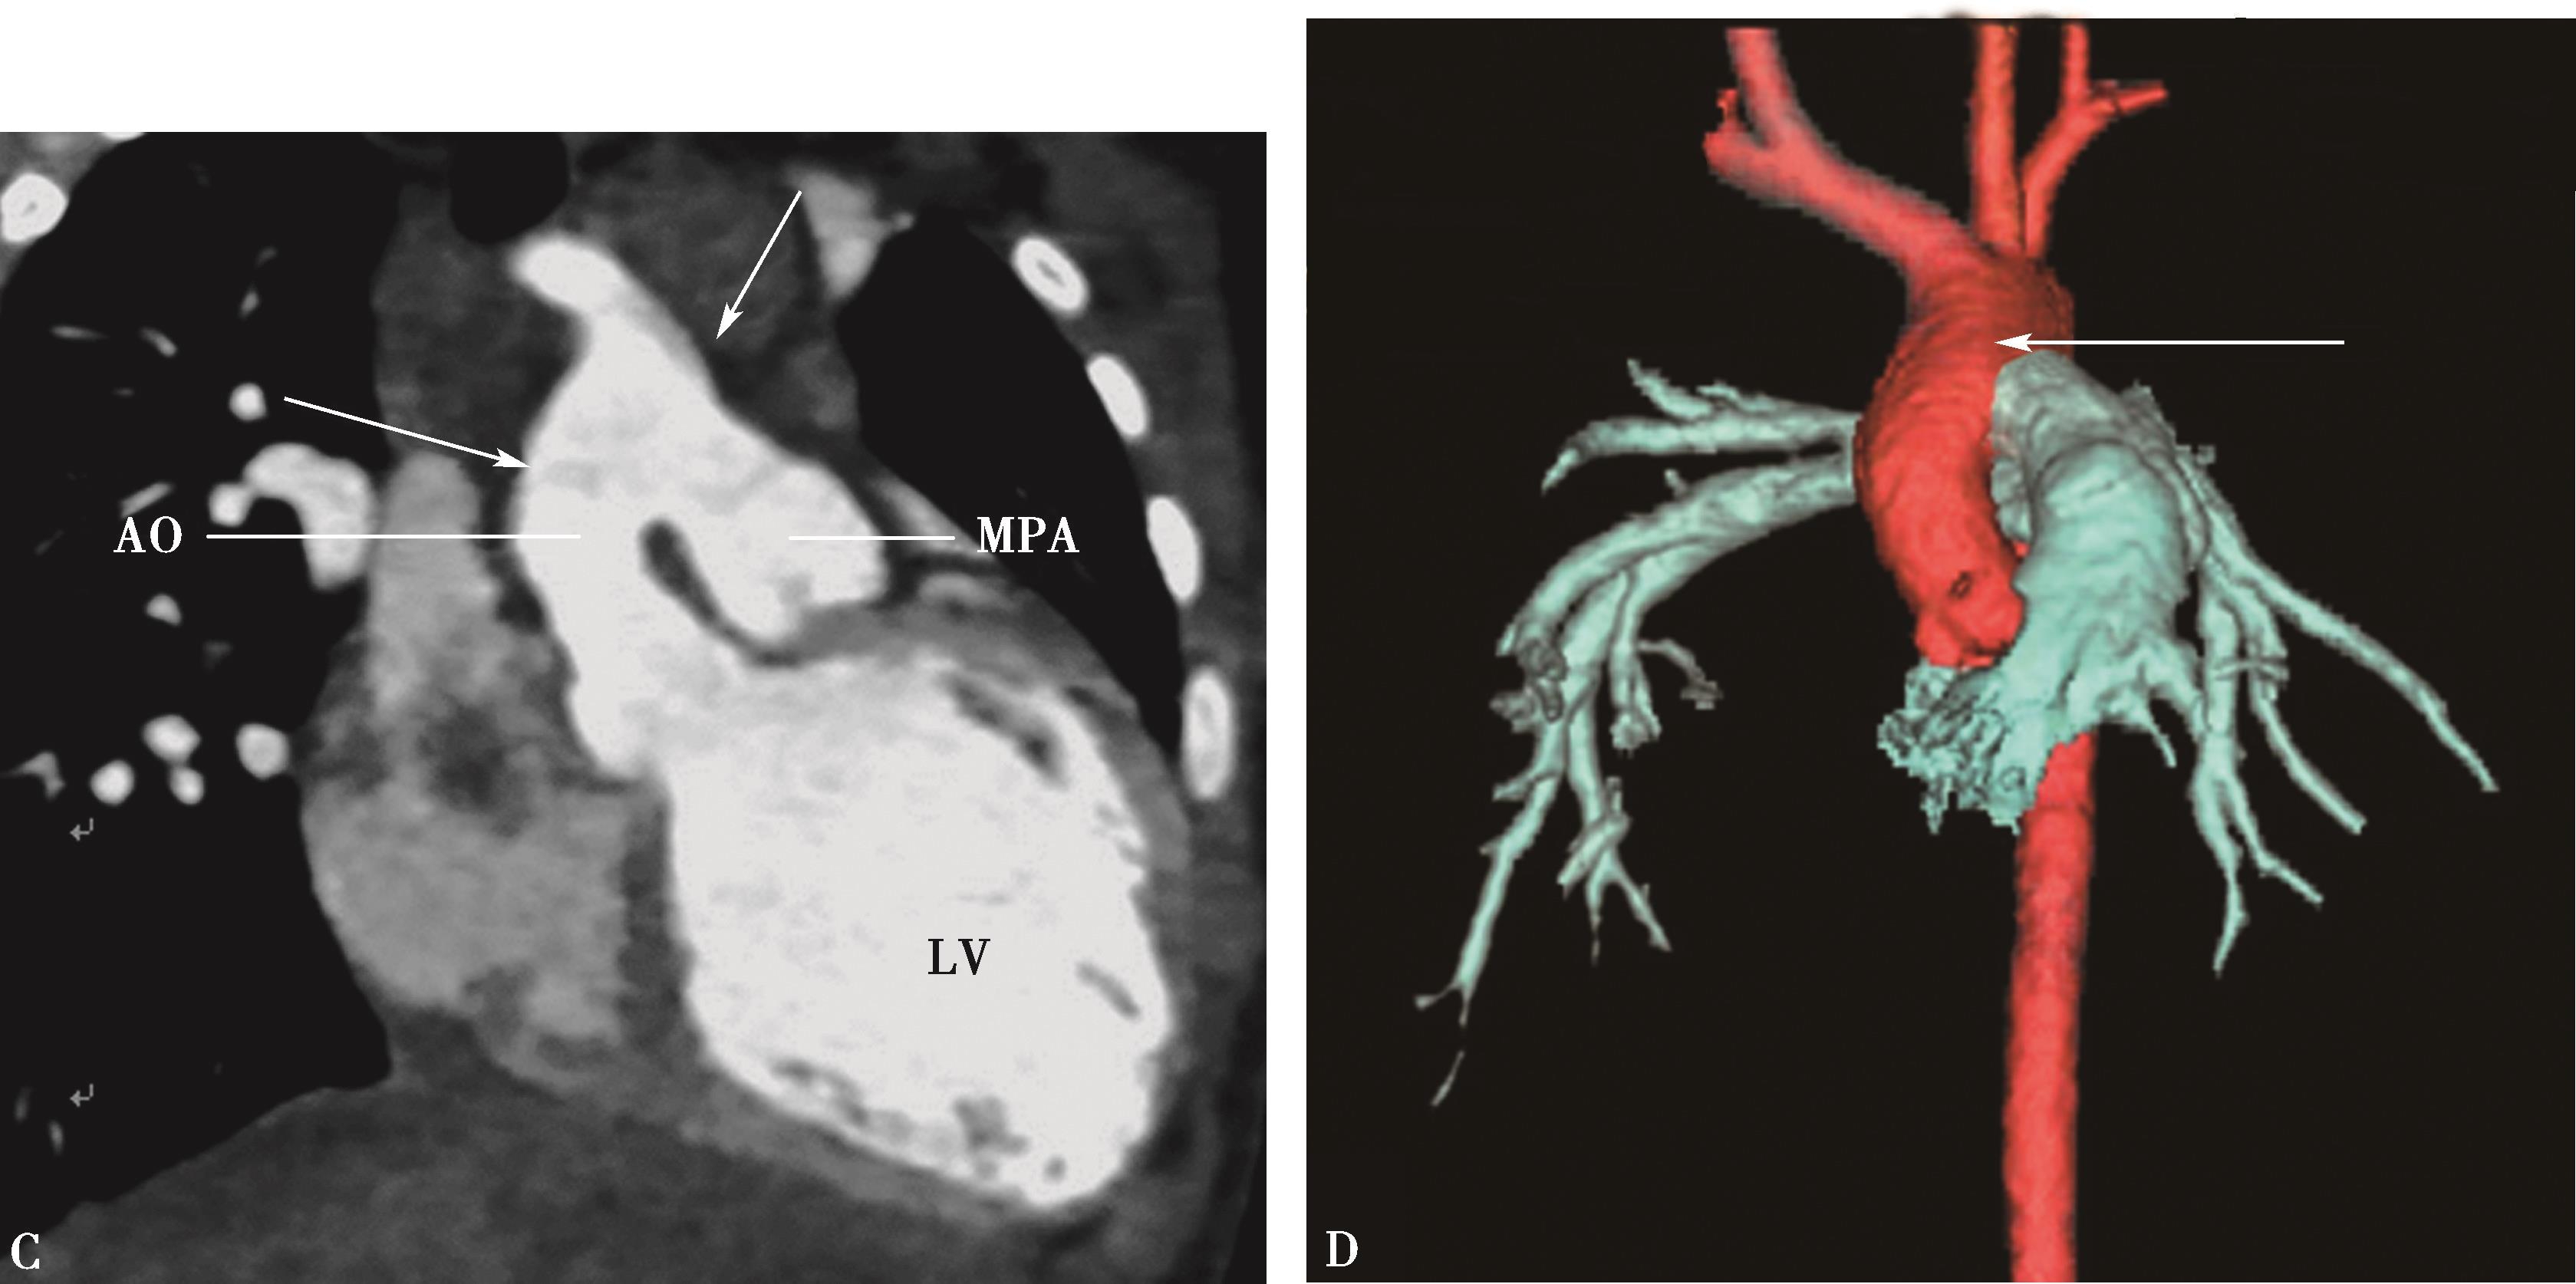

白塞病(Behcet disease,BD)是以血管炎为主要病理基础的慢性多系统疾病。该病与HLA-B51强关联,感染或异常自身免疫应答(尤其是细胞免疫)参与发病。临床上以口腔溃疡、生殖器溃疡、眼炎及皮肤损害为突出表现,又称为口-眼-生殖器综合征。白塞病累及心血管特点为淋巴细胞、浆细胞浸润,弹力纤维破坏,侵犯心脏瓣膜、心内膜炎,累及主动脉瓣、二尖瓣造成瓣叶脱垂、关闭不全;累及房间隔瘤并发血栓形成。累及血管病变特点:①动脉炎呈现淋巴细胞、浆细胞浸润,弹力纤维破坏;动脉瘤形成-真性、假性,游走性、多发性、重复性为其特点,占48%。②静脉炎;急性血栓性静脉炎,占20%;③肺动脉炎:主肺动脉及叶-段动脉分支为该病动脉最易受累的部位,多为动脉瘤形成。

白塞病是肺动脉瘤形成的最常见原因,动脉瘤常伴原位血栓形成。

2.白塞病肺动脉炎CT征象及诊断

(1)横断图像:

白塞病肺动脉炎可累及主肺动脉,左右肺动脉,肺叶-段分支。可以是单发、多发或游走性或复发性。

1)主肺动脉干或/和左右肺动脉干梭形瘤样扩张,腔内不同程度附壁血栓(图8-5-4)。

图8-5-4 反复发作口腔溃疡,临床诊断白塞病

横断图像。A~C.主肺动脉、瘤样扩张,左右肺动脉瘤样扩张,不规则附壁血栓(↑);D~F.三维重建主肺动脉及左右肺动脉瘤样扩张,红色为附壁血栓(↑),波及肺叶分支;CT诊断:肺动脉瘤累及主肺动脉、左右肺动脉及叶分支,附壁血栓形成,病变性质考虑为白塞病

2)肺动脉叶段分支瘤样扩张,真性或假性动脉瘤形成,腔内不同程度附壁血栓(图8-5-5)。

(2)多层重组(MPR)或曲面重组(CPR):

以不同层面、不同角度重建各支肺动脉影像,显示血管病变(动脉瘤)特点、程度、累及范围及附壁血栓特点。

(3)三维重建:

容积再现(VR)或表面阴影显示(SSD):直观显示肺动脉解剖、动脉瘤累及范围。

图8-5-5 男,28岁,反复口腔及生殖器溃疡5年,白塞病,肺动脉瘤

A.胸部X线片,示左右肺动脉瘤(↑);B.横断图像,左、右下肺动脉动脉瘤形成,附壁血栓形成(↑);C.多层重组(冠状位)示右下肺动脉动脉瘤合并附壁血栓(↑);D.多层重组(左前斜位)示左下肺动脉瘤合并附壁血栓形成(↑)。CT诊断:左右肺动脉瘤,附壁血栓形成,病变性质白塞病